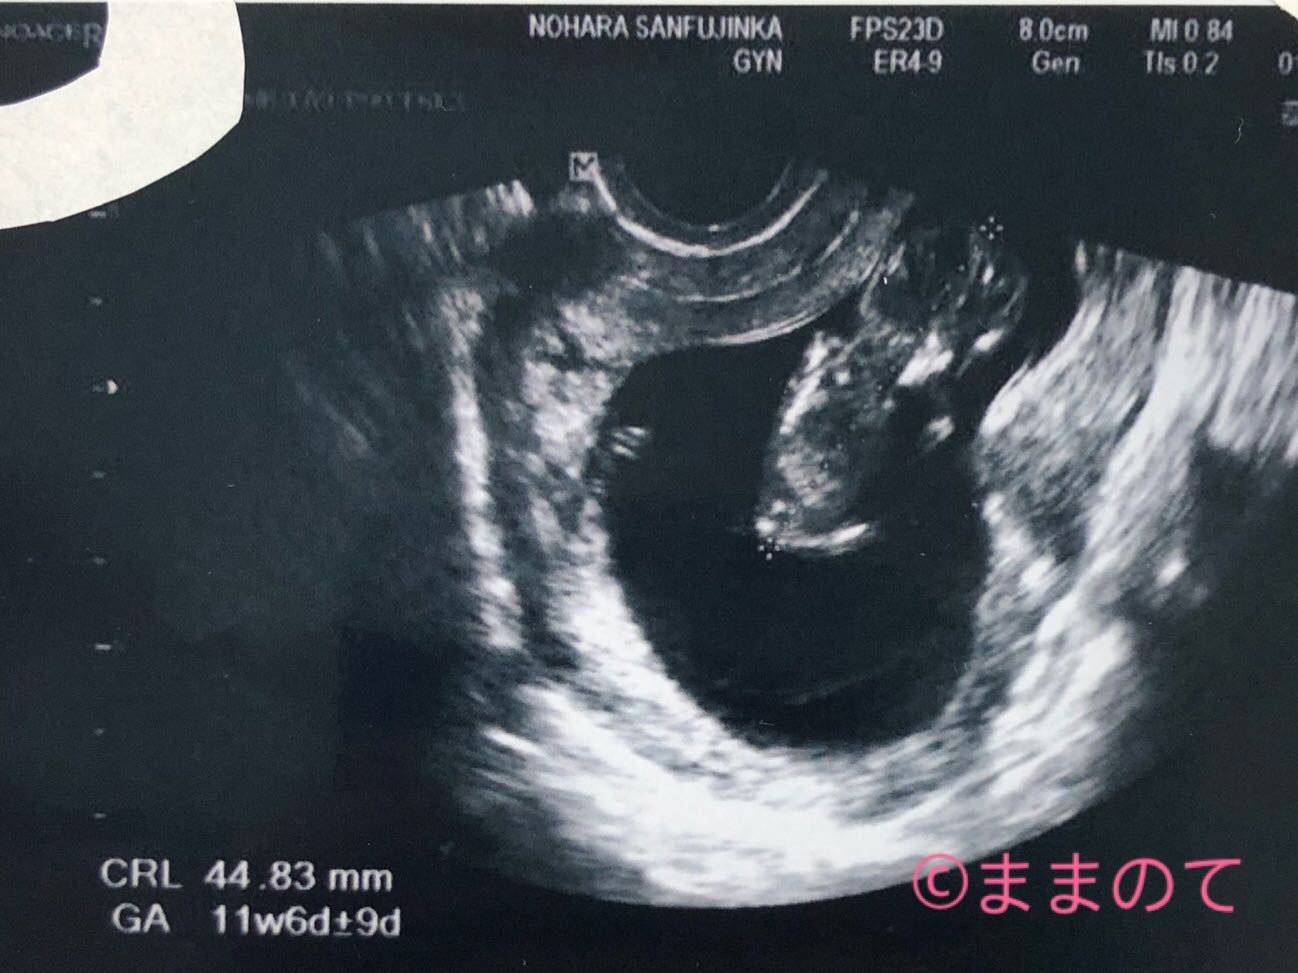

妊娠11週の赤ちゃんのエコー画像

11週6日のエコー写真です。右上に頭があります。小さな手足がかわいらしいですね。